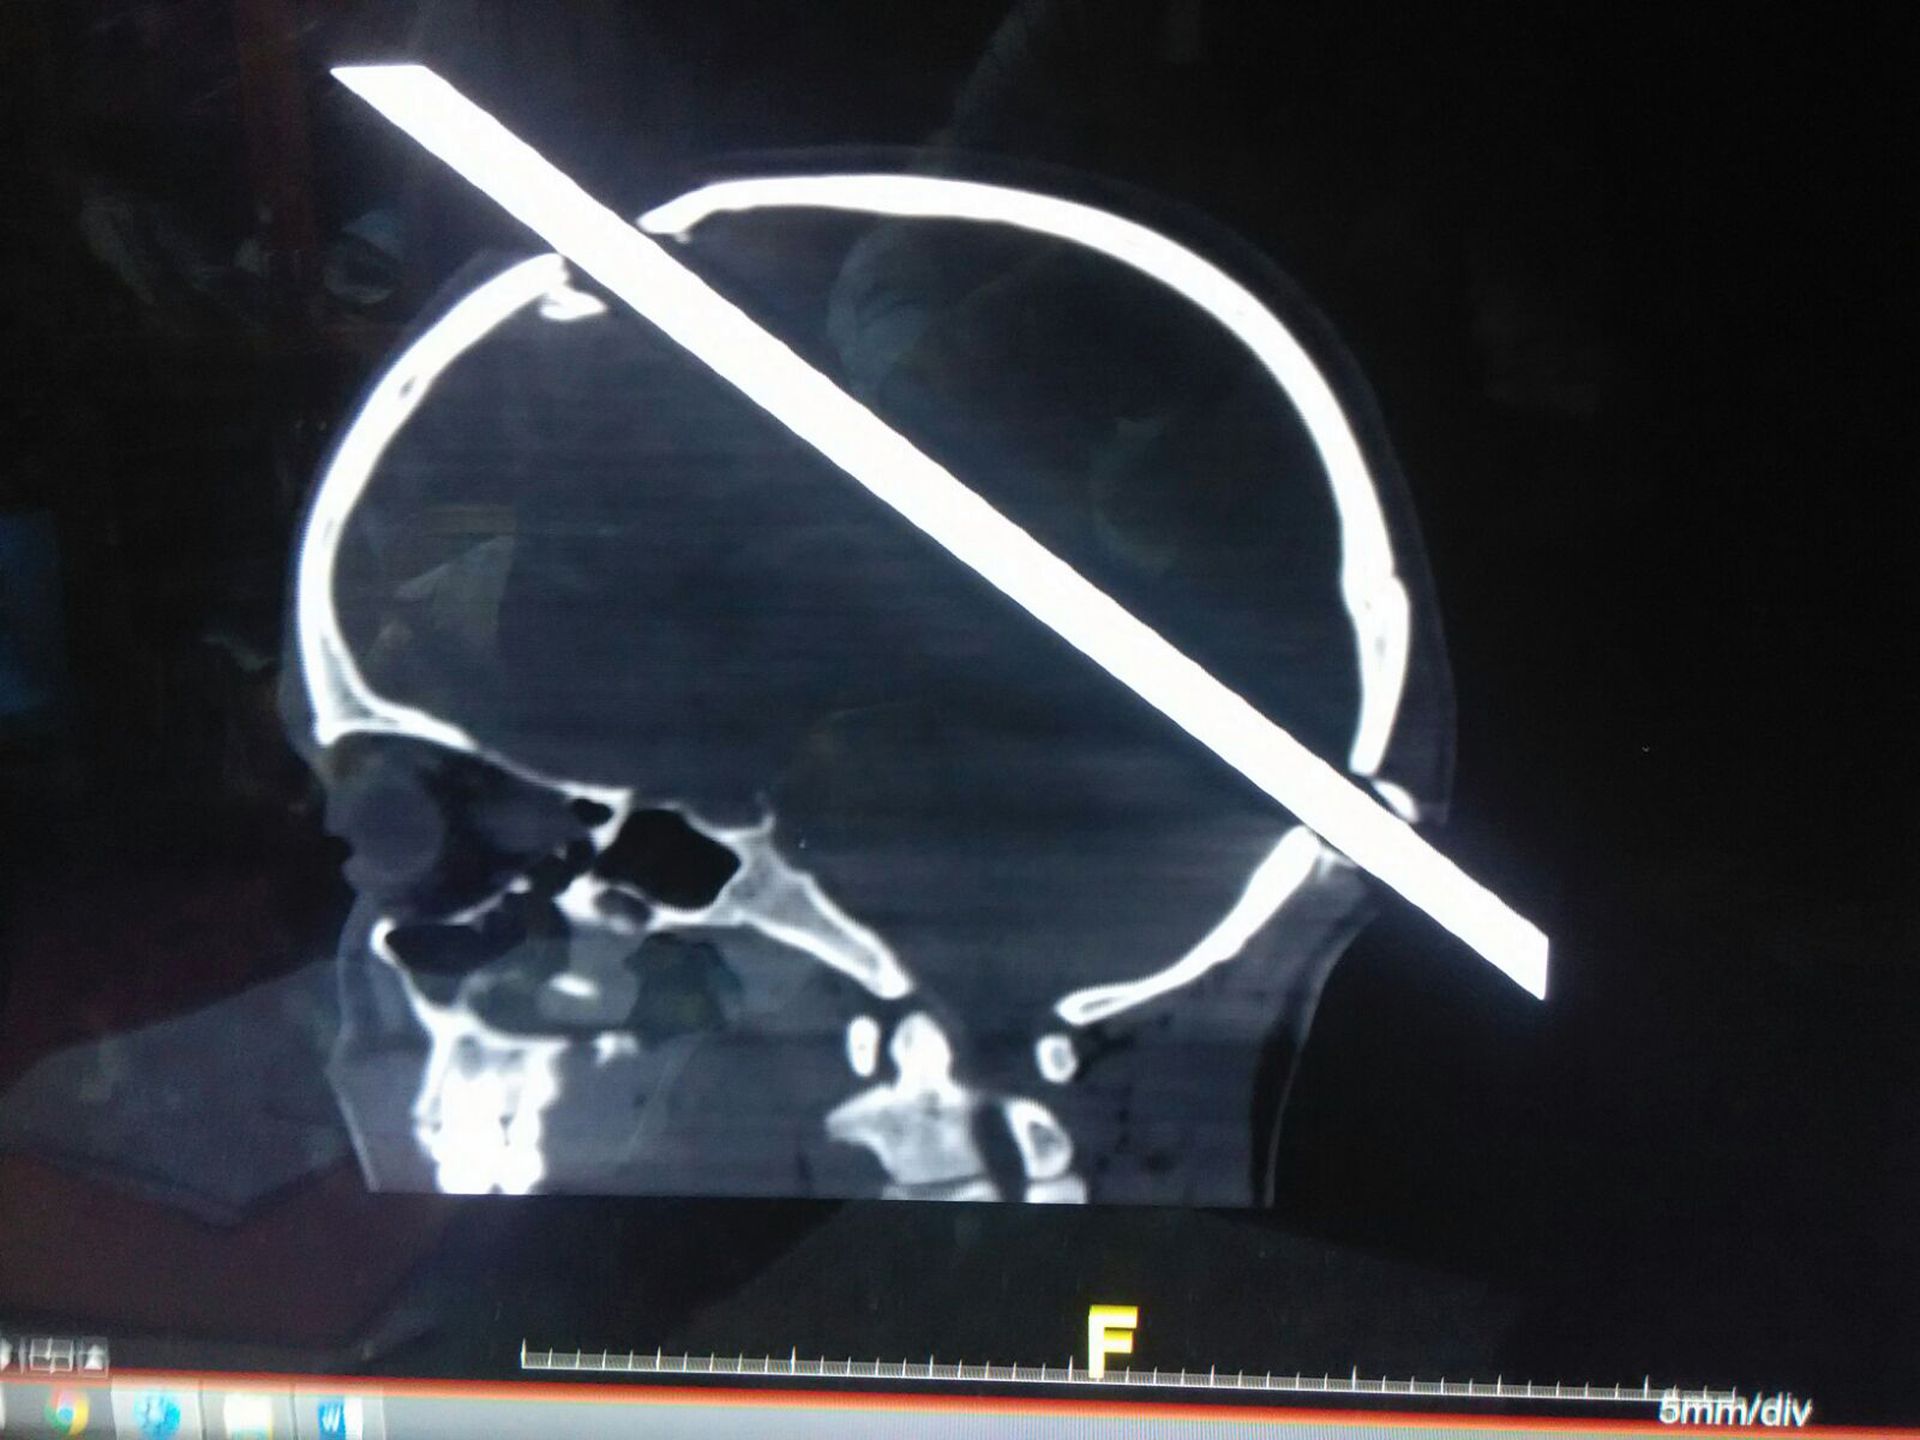

24-letni robotnik z Malad w Indiach trafił do szpitala. Pręt, który przeszył mu głowę, miał dwa metry długości.

Na zdjęciu z rentgena widać, w którym miejscu pręt wbił się w głowę Guddu.